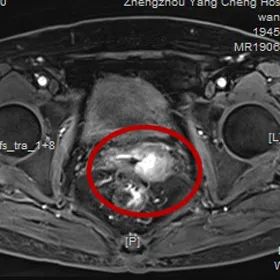

經(jīng)過婦科檢查

發(fā)現(xiàn)宮頸菜花樣腫物

結(jié)合MRI影像

細(xì)胞學(xué)檢查

被確診為

宮頸癌

經(jīng)過多次的放療

樊阿姨的陰道出血癥狀

及宮頸菜花樣腫物

在逐漸改善和變小